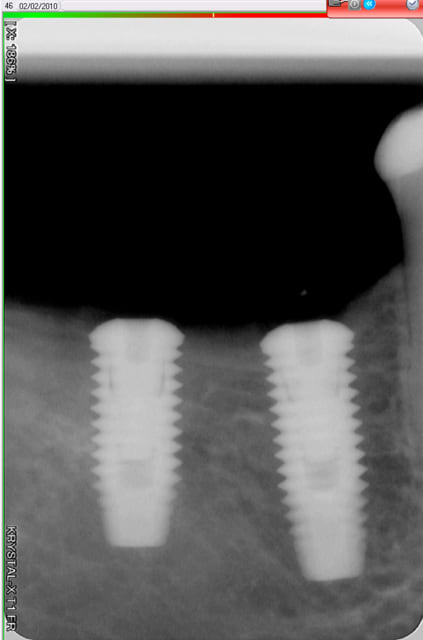

j'ai posé deux easy avec le biseau enfoui dans l'os. A 3 mois, pose des piliers de cicatrisation et un mois plus tard pose de la prothèse.

manifestement l'os ne reste pas en place à ce niveau

je prendrai un cliché dans 3 mois pour évaluer ce qu'il advient de la zone mésiale du col de l'implant distal.